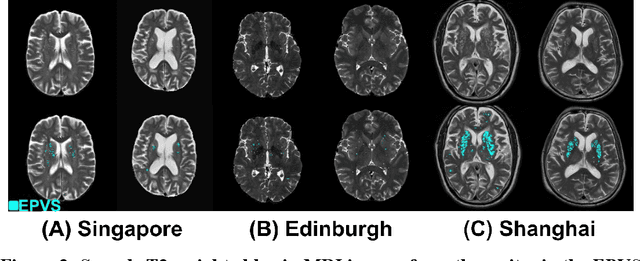

Abstract:Perivascular spaces (PVS), when abnormally enlarged and visible in magnetic resonance imaging (MRI) structural sequences, are important imaging markers of cerebral small vessel disease and potential indicators of neurodegenerative conditions. Despite their clinical significance, automatic enlarged PVS (EPVS) segmentation remains challenging due to their small size, variable morphology, similarity with other pathological features, and limited annotated datasets. This paper presents the EPVS Challenge organized at MICCAI 2024, which aims to advance the development of automated algorithms for EPVS segmentation across multi-site data. We provided a diverse dataset comprising 100 training, 50 validation, and 50 testing scans collected from multiple international sites (UK, Singapore, and China) with varying MRI protocols and demographics. All annotations followed the STRIVE protocol to ensure standardized ground truth and covered the full brain parenchyma. Seven teams completed the full challenge, implementing various deep learning approaches primarily based on U-Net architectures with innovations in multi-modal processing, ensemble strategies, and transformer-based components. Performance was evaluated using dice similarity coefficient, absolute volume difference, recall, and precision metrics. The winning method employed MedNeXt architecture with a dual 2D/3D strategy for handling varying slice thicknesses. The top solutions showed relatively good performance on test data from seen datasets, but significant degradation of performance was observed on the previously unseen Shanghai cohort, highlighting cross-site generalization challenges due to domain shift. This challenge establishes an important benchmark for EPVS segmentation methods and underscores the need for the continued development of robust algorithms that can generalize in diverse clinical settings.